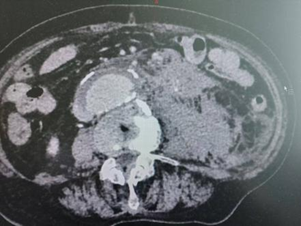

术前

据悉,该名 87 岁老年男性患者于当日凌晨被家人发现晕厥,清醒后紧急前往外院就诊。入院时,患者血压已降至 60/40mmHg,意识模糊,情况危急。经影像学检查后,患者被确诊为腹主动脉瘤破裂、腹腔积液 / 血—— 这是血管外科领域极为凶险的急症,一旦发病,短时间内就可能因大量失血危及生命,被称为人体血管里的 “不定时炸弹”。由于患者年龄极高,且合并心功能差、呼吸功能不全等基础问题,外院评估后认为手术风险极高。为寻求更优质的救治,患者家属决定将其转入我院介入与血管外科。